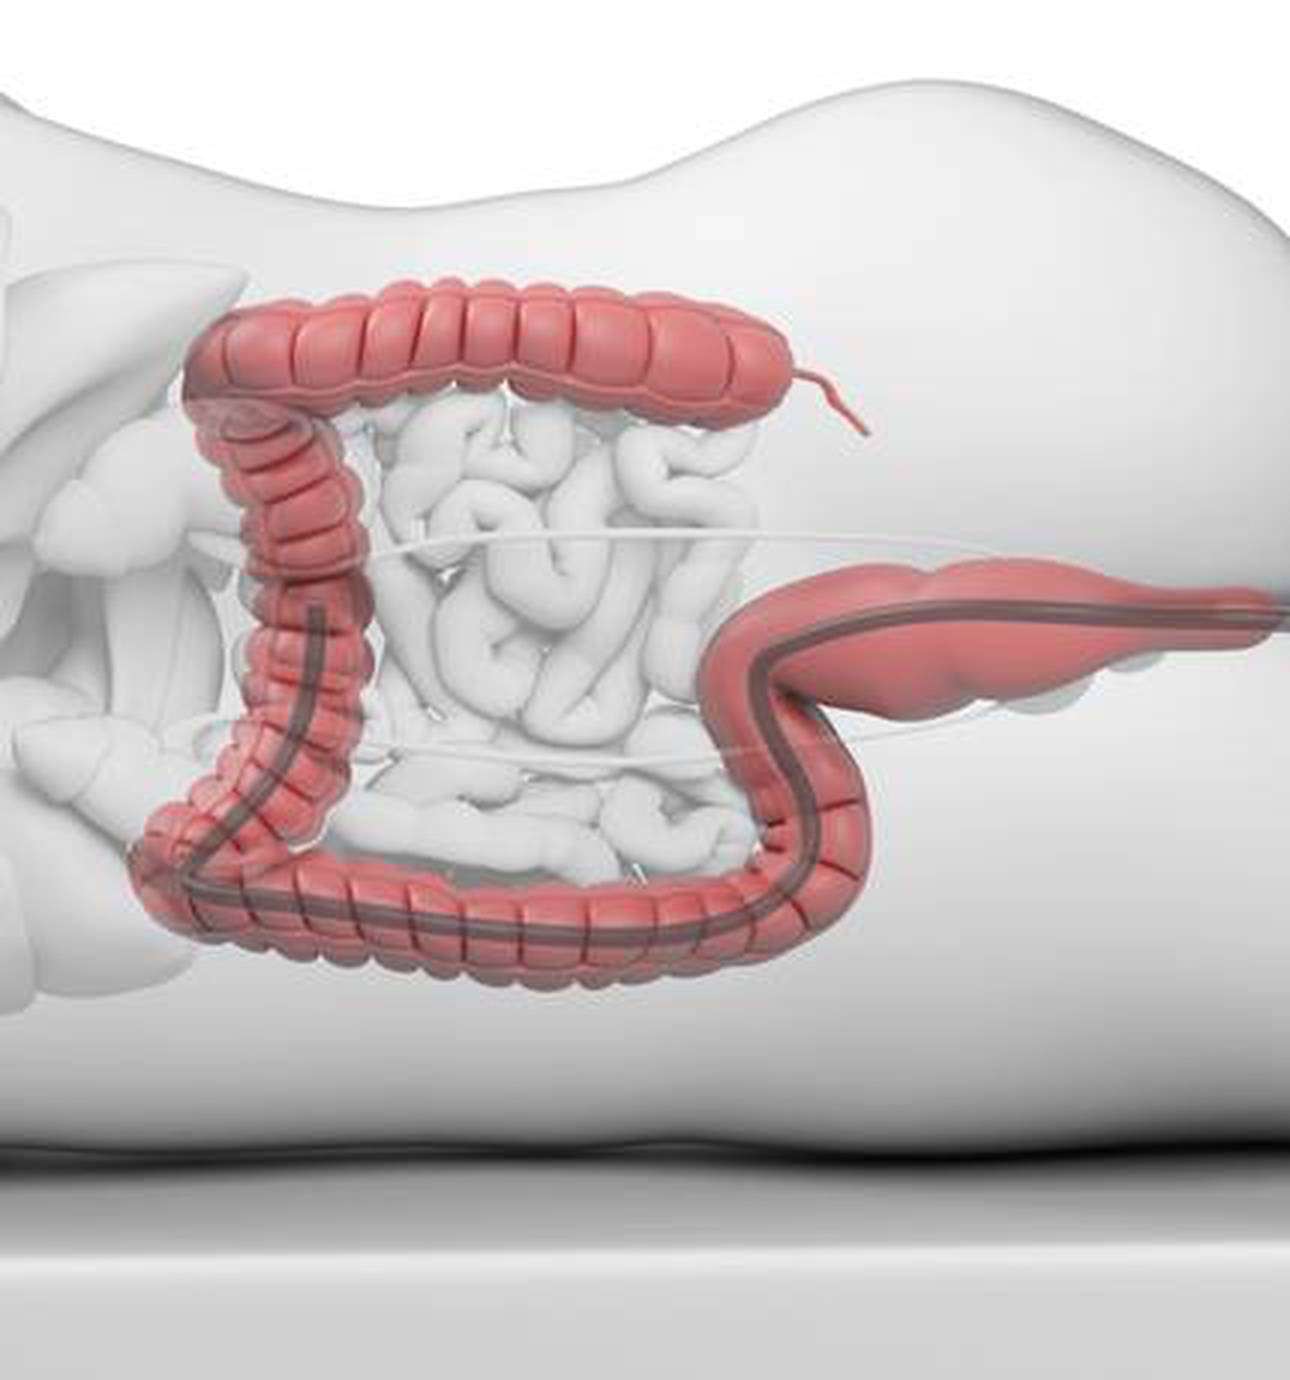

The surgical work at St Mark’s Hospital specialises in advanced techniques for the treatment of both common and unusual problems of the small and large bowel and of the anus.

The Lennard Jones Intestinal Rehabilitation Unit at St Mark’s Hospital is a specialist centre dedicated to the assessment and management of patients with intestinal failure.